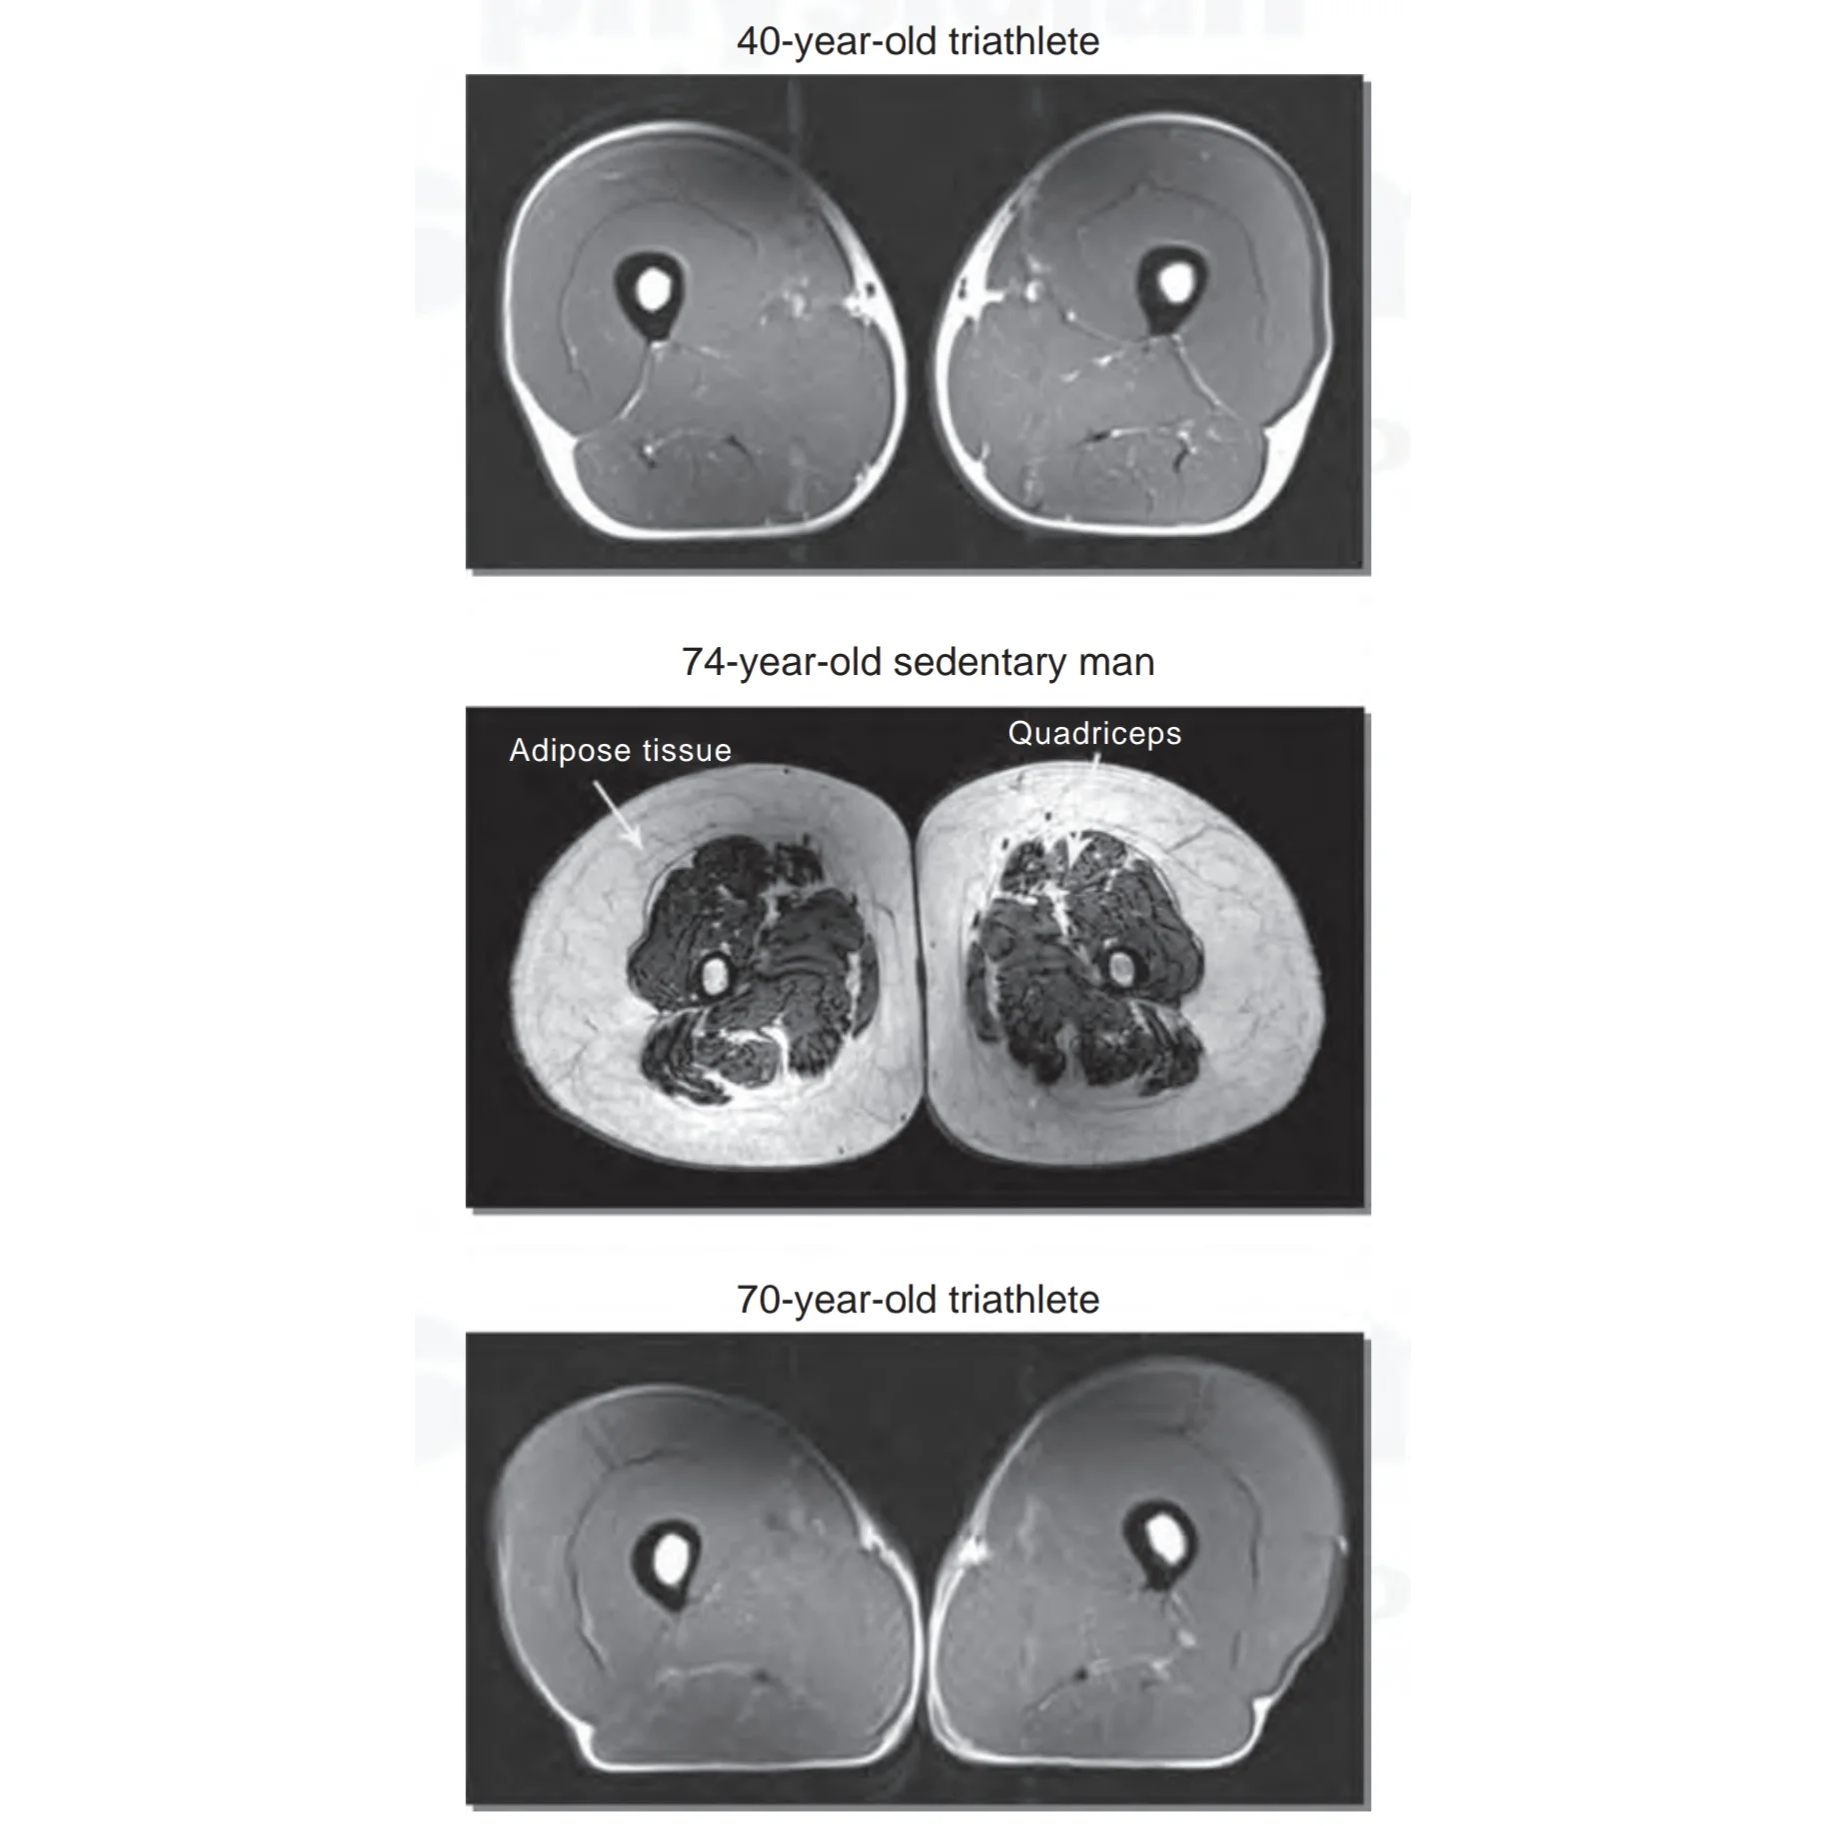

Muskler åldras inte – om du tränar. Här är beviset.

Det är en utbredd uppfattning att vi oundvikligen förlorar muskelmassa med åldern. Men forskning visar att det inte nödvändigtvis stämmer. En amerikansk studie ledd av Dr. Wroblewski undersökte jus...